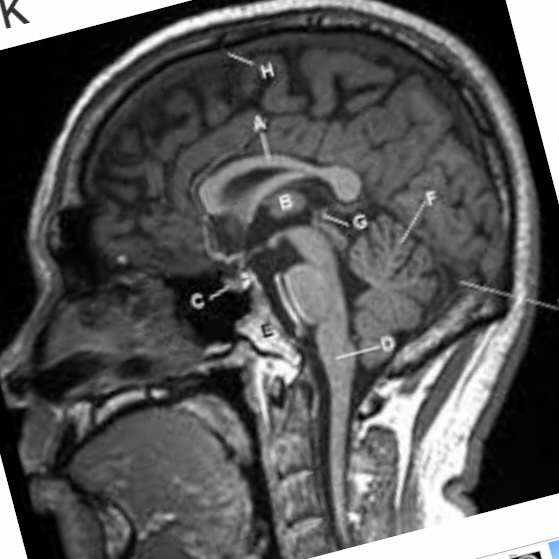

They still haven’t studied brain mass, likely never will because muh racism. Using our eyeballs we can see that the frontal lobe is smaller and the whole brain shape is different.

Not really. No study has been done specifically on frontal brain volume. On overall brain volume, black people have a smaller brain so we’d expect it to be smaller than whites if they compared it. But let’s say overall brain mass means nothing; like I said, using our eyeballs we can see the shape is different as well.Did I or did I not debunk your theory on brain volume composition differences in the prefrontal cortex

If we analyze a Black persons cranofacial structure, we can see protrusion of the occipital lobe.

This indicates a lack of frontal lobe development. In comparison to white people, who have a flatter occipital lobe but more of a higher frontal lobe region.

Indeed, the differences between the races are visible just by looking at the cranium. White people are more capable of long-term planning, logic, and critical thinking and judgement, due to their more developed frontal lobe.

The occipital lobe is good for moving of the muscles, sense of rhythm, and indeed may result in a person that seems “stronger” or “healthier”. After all, this large frontal lobe is a new development (past 50-100,000 years) that we likely haven’t fully evolved to handle and appreciate, as we don’t sexually select people who stay inside thinking all day, but rather those who go outside and socialize.